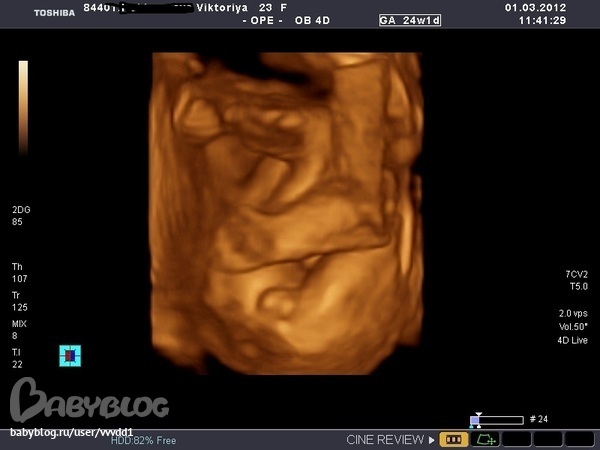

Вопросы про УЗИ, обследования и анализы: что, где, как, когда?Девченки,кто разбирается,посмотрите на фотку,как вы думаете это девочка или мальчик?Мне 2 врача сказали девочка,а родственники мои задурили мне голову,все хорохом говорят,что это похоже на достоинство мальчика,муж тоже так считает,я начинаю теперь сомневаться.Если есть возможность,покажите фотку мальчика.

Викусь, это девчушечка! По второй фотке видно, что нет писюна

Я решила пойти еще раз на узи удостовериться,а то будет финиш,набрала розовой одежки,а скажут мальчик))))гламурный тогда будет,мне все мои доказывают,что это яички))))

Мне кажется, что мальчик. Но Узист знает лучше, ведь половые органы мальчика и девочки расположены под разным углом.